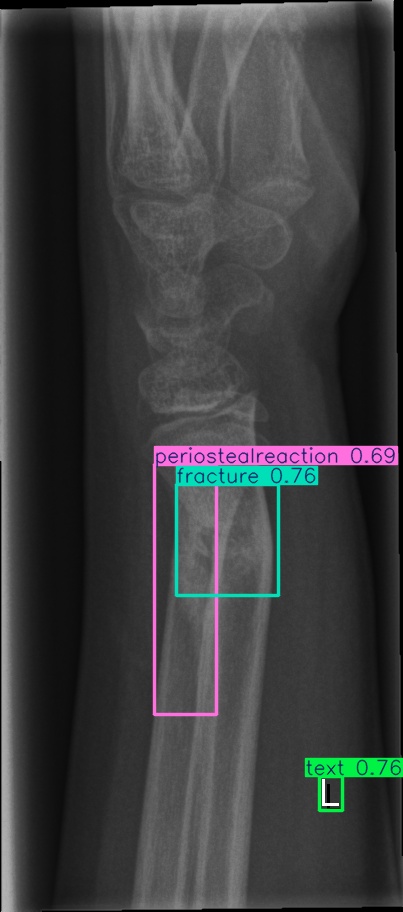

For our experiments, we selected the GRAZPEDWRI-DX images with bounding box annotations in YOLO format, which contains nine classes. Following the data division and augmentation approach outlined by [10], the dataset was randomly divided into 70%70\% training (14,23414,234 images), 20%20\% validation (4,0654,065 images), and 10%10\% testing (2,0282,028 images) sets. To further augment the training data, the number of images in the training set was doubled by adjusting the contrast and luminance of the images. The label distribution and bounding box statistics are shown in Figure 3. Examples of two training images with bounding box annotations from the GRAZPEDWRI-DX dataset are shown in Figure 4.

Refer to caption

Figure 4: Bounding box-annotated X-ray images of pediatric wrist trauma from the GRAZPEDWRI-DX dataset [8].

Figure 8: Sample of five images from the GRAZPEDWRI-DX test set, displaying ground-truth and predicted bounding box annotations: (a-e): ground-truth annotations, (f-j): YOLOv11l annotations, and (k-o): G-YOLOv11 annotations.

Table 4: Confidence scores predicted by YOLOv11l and the proposed G-YOLOv11l detectors for five images from the GRAZPEDWRI-DX test set, PR: pronator sign, FP: False positive.

8(e) fracture, periosteal reaction, text 0.760.76, 0.690.69, 0.760.76 0.750.75, 0.600.60, 0.760.76

The results in Table 4, derived from Figure 8, compares the confidence scores predicted by YOLOv11l and G-YOLOv11l detectors for five test images from the GRAZPEDWRI-DX dataset. Figure 8 contrasts ground-truth annotations with predictions from YOLOv11l and G-YOLOv11l. G-YOLOv11l shows slight improvements, such as higher confidence scores for "fracture" and "metal" in Figure 8(a) (0.700.70 and 0.890.89 vs. 0.670.67 and 0.860.86) and for "text" in Figure 8(b) (0.730.73 vs. 0.710.71). However, limitations include false positives, such as for "pronator sign" in Figure 8(c) (score 0.440.44), and lower confidence for some instances, as seen in Figures 8(d) and 8(e). While G-YOLOv11l demonstrates competitive performance, further refinements are required to improve its robustness.